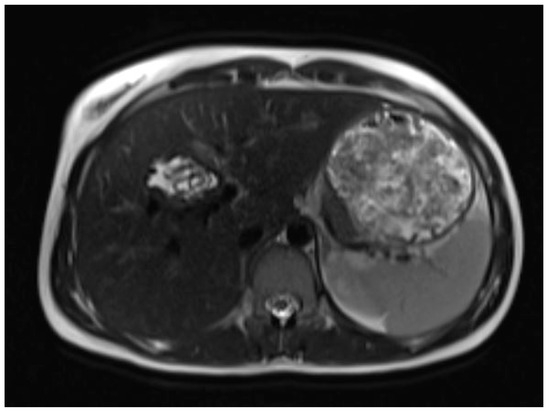

A liver MRI scan confirmed a cystic structure with multiple daughter cysts, hypointense on a T1-weighted image (T1WI), and hyperintense on a T2-weighted image (T2WI), with no solid components, no signs of membrane rupture, and a maximum diameter of 10 cm (craniocaudal) (Figure 1). Additionally, elevated signals on T2WI in the surrounding liver tissue were found. The T1 sequences did not reveal any contrast uptake after 5 (Figure 2), 10, or 20 (Figure 3) minutes post-injection. Furthermore, DWI/ADC mapping indicated a hydatid cyst. The DWI sequences included a trace DWI (Figure 4), an ADC map (Figure 5), and both at b800. Radiomics and AI tools were not involved. The trace DWI showed an area of hypointensity in the region of the cyst that was surrounded by a hypointense layer, depicting the cystic wall. The ADC map revealed hyperintensity within the area, in concordance with a typical depiction of cysts on an MRI scan.

Figure 2.

First MRI scan: Axial T1W MRI scan showing hypointense daughter cysts in liver segment IV with no contrast uptake after 5 min.

MR imaging clearly visualizes pericyst, matrix, and daughter cysts. The pericyst appears as a hypointense rim on both T1WI and T2WI due to its fibrous structure and the presence of calcifications. This is a specific feature of hydatid cysts, called the rim sign, mostly better visualized on T2WI [5]. The matrix represents hydatid-fluid-containing membranes of broken daughter vesicles, scolices, and hydatid sand [7]. The hydatid matrix appears hypointense on T1WI and significantly hyperintense on T2WI. However, the limitations of MRI scans are especially observed in stages CE4–CE5, as bigger calcifications are better observed on a CT scan. When daughter cysts are present, they are typically more hypointense than the matrix on T2WI, as observed in our case report [17] (Figure 1). If the membrane is separated, it can shift with movement, resembling a water lily floating on the surface of a pond, previously described as water-lily sign, which was seen in our case report as well [18] (Figure 8).